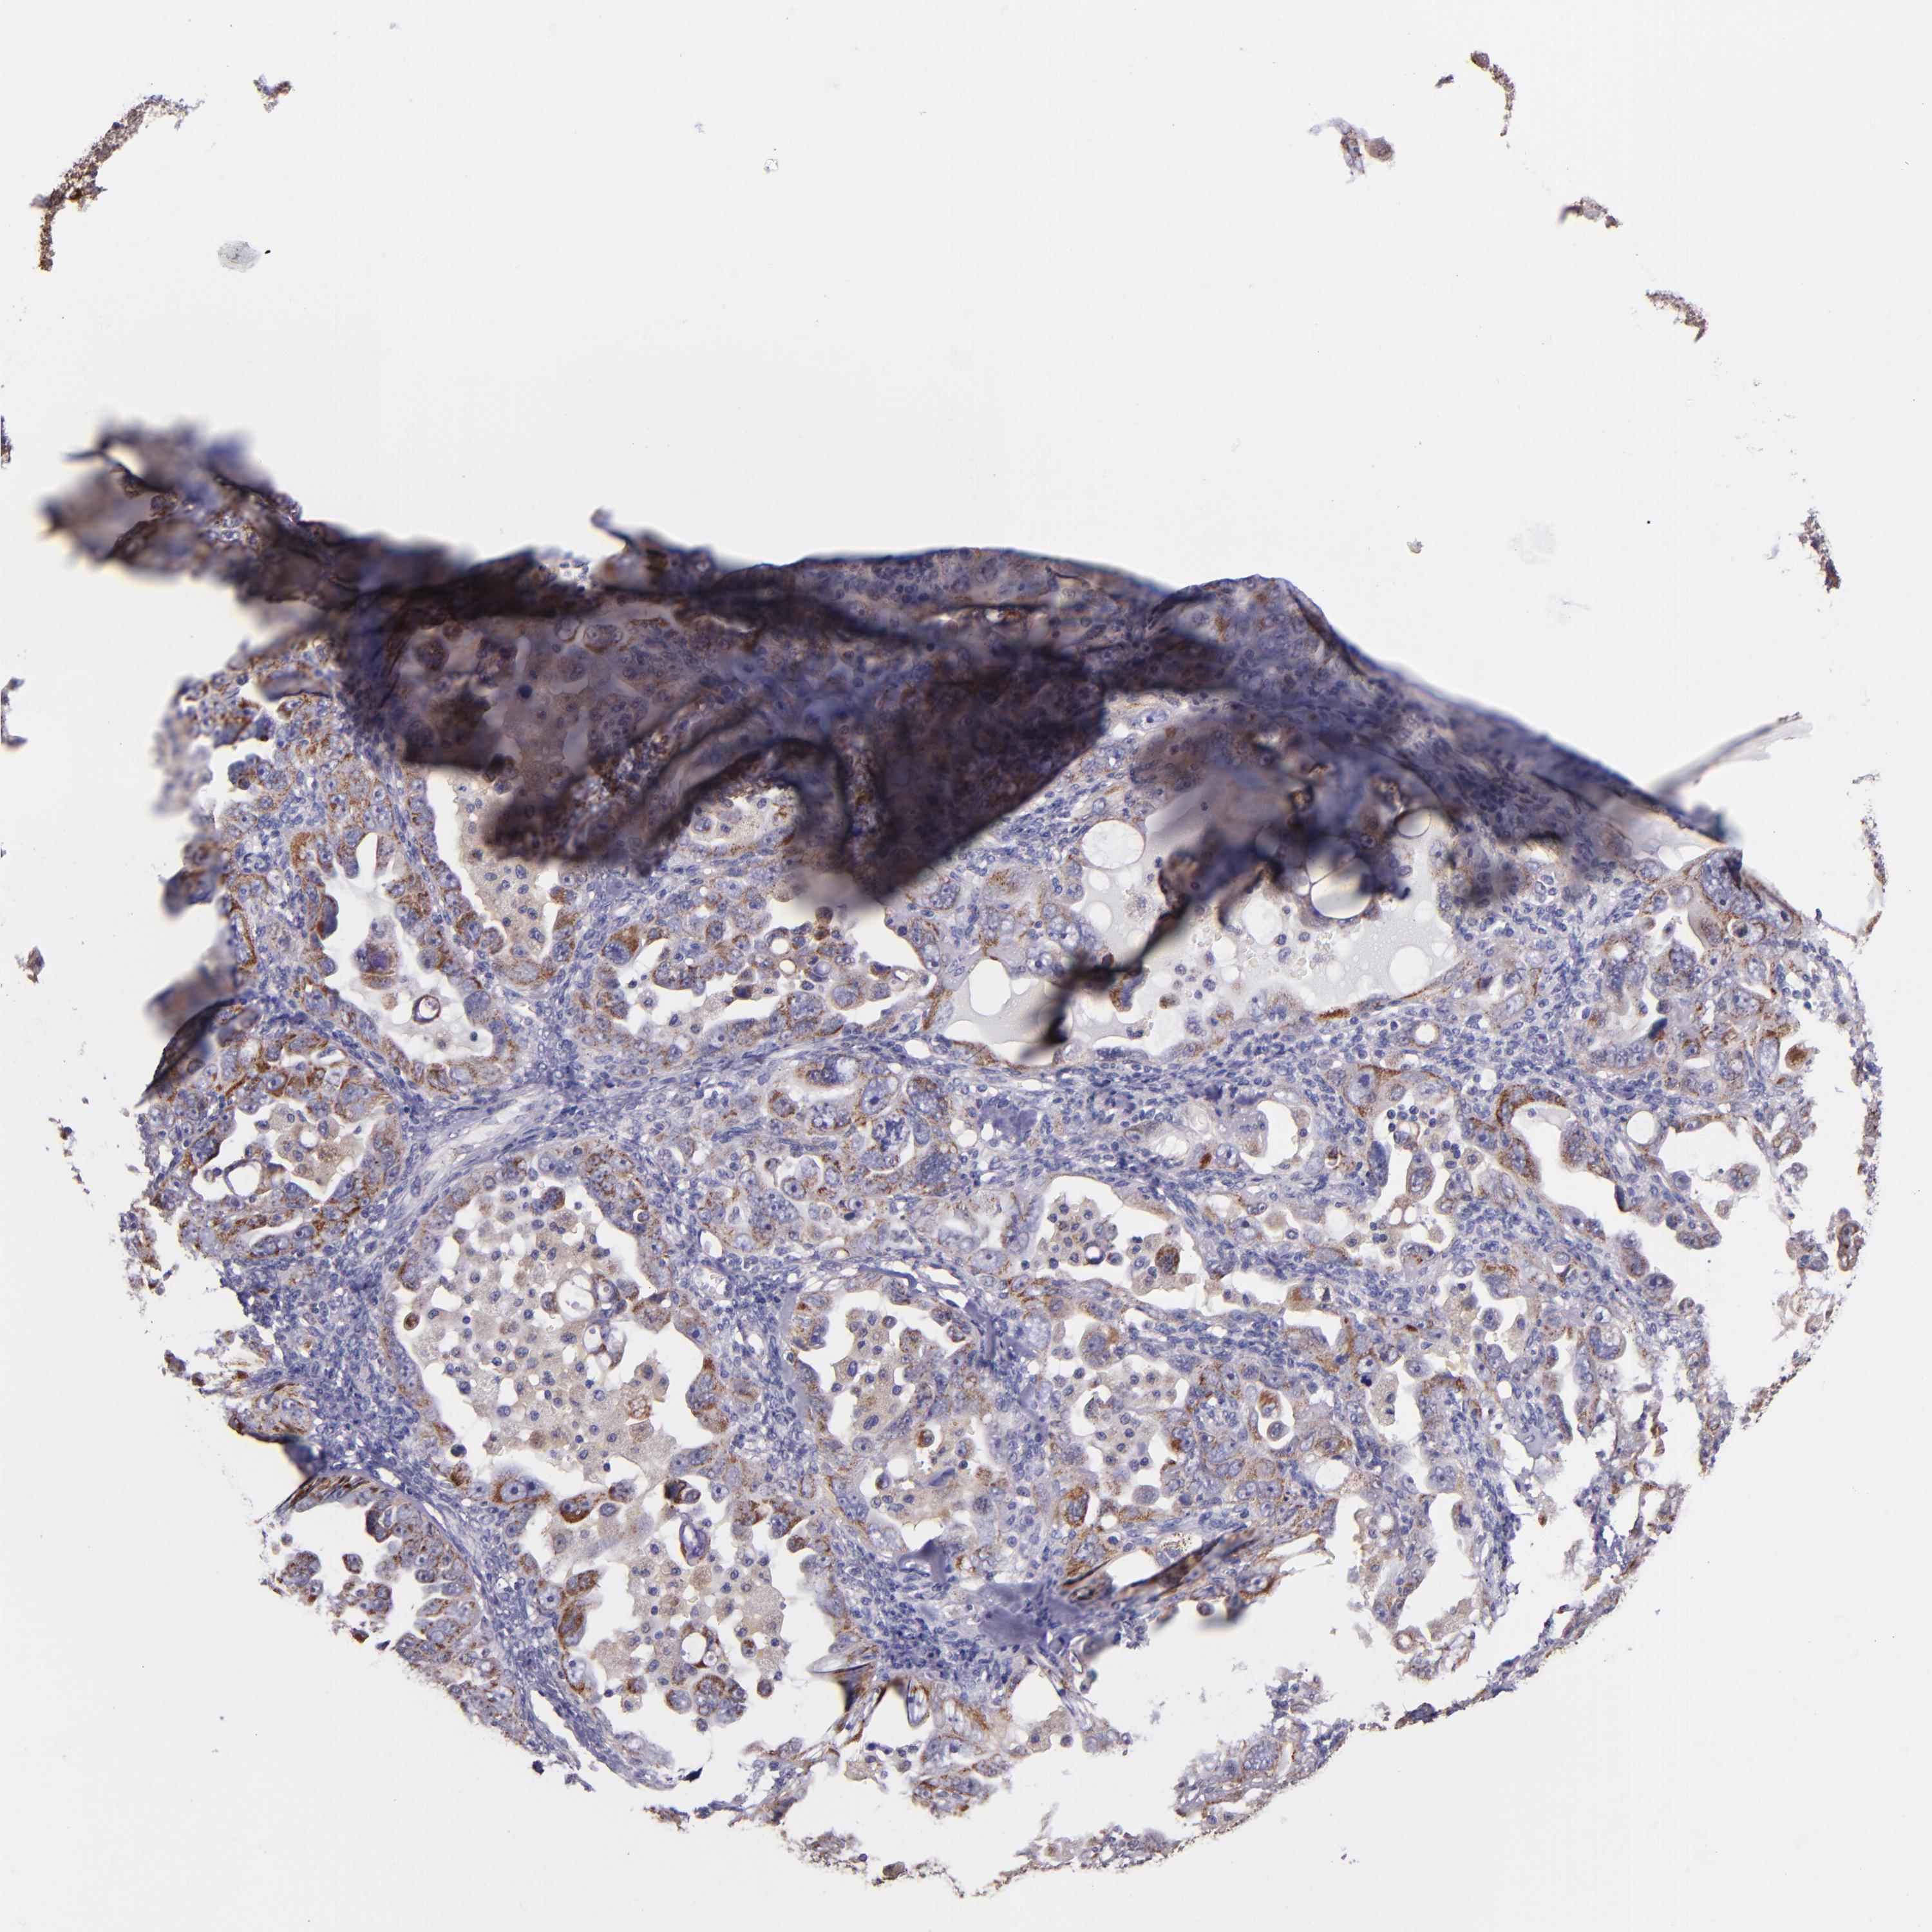

OVARIAN CANCER - Protein expressioni

A mouse-over function shows sample information and annotation data. Click on an image to view it in a full screen mode. Samples can be filtered based on level of antibody staining by selecting one or several of the following categories: high, medium, low and not detected. The assay and annotation is described here.

Note that samples used for immunohistochemistry by the Human Protein Atlas do not correspond to samples in the TCGA dataset.

Antibody stainingi

Antibody staining in the annotated cell types in the current human tissue is reported as not detected, low, medium, or high, based on conventional immunohistochemistry profiling in selected tissues. This score is based on the combination of the staining intensity and fraction of stained cells.

Each image is clickable and will lead to virtual microscopy that enables deeper exploration of all samples and also displays staining intensity scores, fraction scores and subcellular localization as well as patient and tissue information for each sample.

Antibody HPA001844

Antibody CAB005374

Antibody CAB016305

Cystadenocarcinoma, serous, NOS

Cystadenocarcinoma, mucinous, NOS

Carcinoma, endometroid

Carcinoma, NOS